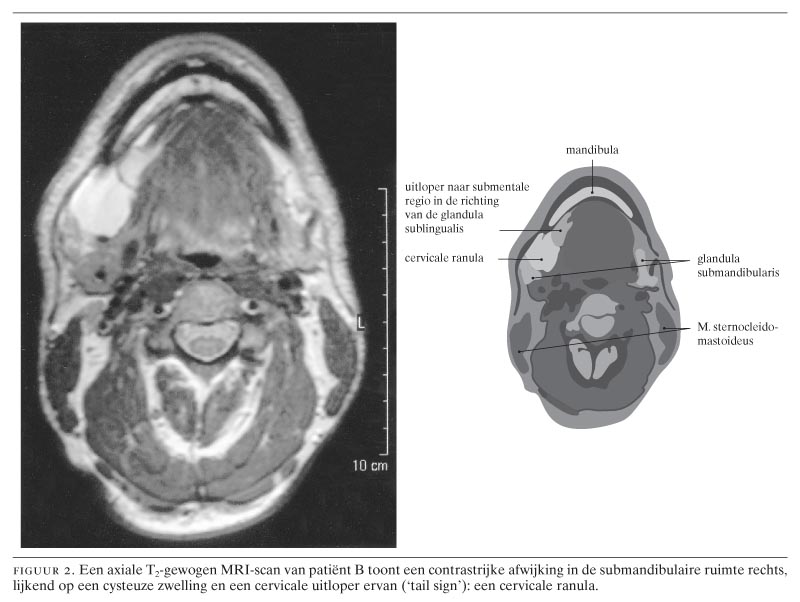

Drie patiënten, 2 mannen van 21 en 39 jaar en 1 vrouw van 29 jaar, presenteerden zich met een unilaterale zwelling in de hals zonder begeleidende symptomen. Bij de jongste man werd de diagnose ‘cervicale ranula’ (‘plunging ranula’) gesteld nadat bij (herhaalde) punctie een helder gelig taai secreet was verkregen met een hoge amylaseactiviteit. Bij de oudste man kwam deze aandoening tijdens een halsexploratie aan het licht en bij de vrouw pas na 2 operatieve ingrepen. Bij alle 3 trad er na verwijdering van de betreffende speekselklieren geen recidief op. Een cervicale ranula is een uitbreiding van een pseudo-cyste van de glandula sublingualis. Belangrijke aanwijzingen daarvoor zijn: een gelijktijdig of in het verleden aanwezige ranula in de mondbodem, een op de MRI- of CT-scan zichtbare cysteuze massa in de submandibulaire ruimte met een uitloper naar de sublinguale ruimte en een verhoogde amylaseactiviteit in punctiemateriaal. De behandeling bestaat uit het elimineren van het speeksel door extirpatie van de glandula sublingualis, waarbij de cervicale component intraoraal wordt gedraineerd. Vanwege het pseudo-cysteuze aspect van de zwelling in de hals is lokale excisie van een cervicale ranula zinloos.